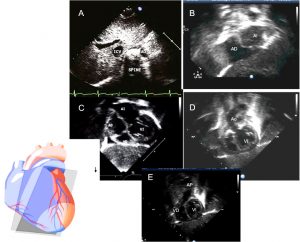

Plano subcostal

– Posición de la sonda: situarla inmediatamente por debajo del apéndice xifoides, en posición neutra, con la muesca del transductor orientada hacia la izquierda del niño Partiendo de esta posición se va realizando basculación cefálica, con lo que iremos visualizando progresivamente las posiciones longitudinales posterior, media y anterior.

– Utilidad del plano: Determinación del situs visceral: el estudio ecocardiográfico se suele comenzar con la determinación del situs visceral (Figura A), que se obtiene mediante el eje largo del plano subcostal.

El término situs visceral se refiere a la disposición de las vísceras tóraco-abdominales con respecto a la línea media. En el situs solitus (normal), se identifican el hígado a la derecha, el bazo y el estómago a la izquierda; el ápex cardíaco en el hemitórax izquierdo (levocardia) y dirigido hacia la izquierda (levoápex); además deben visualizarse la vena cava inferior y la arteria aorta descendente, encontrándose esta última en posición posterior-izquierda en relación a la vena cava. Las anomalías del situs se pueden asociar a cardiopatías congénitas complejas y graves.

También es el plano que en su posición más posterior permite visualizar el tabique interauricular (Figura B, ver videos: se pueden observarse defectos interauriculares a este nivel).

A nivel medial veremos la conexión de aorta con ventrículo izquierdo (Figura D) y más anterior la disposición del ventrículo derecho conectado con la pulmonar (Figura E).